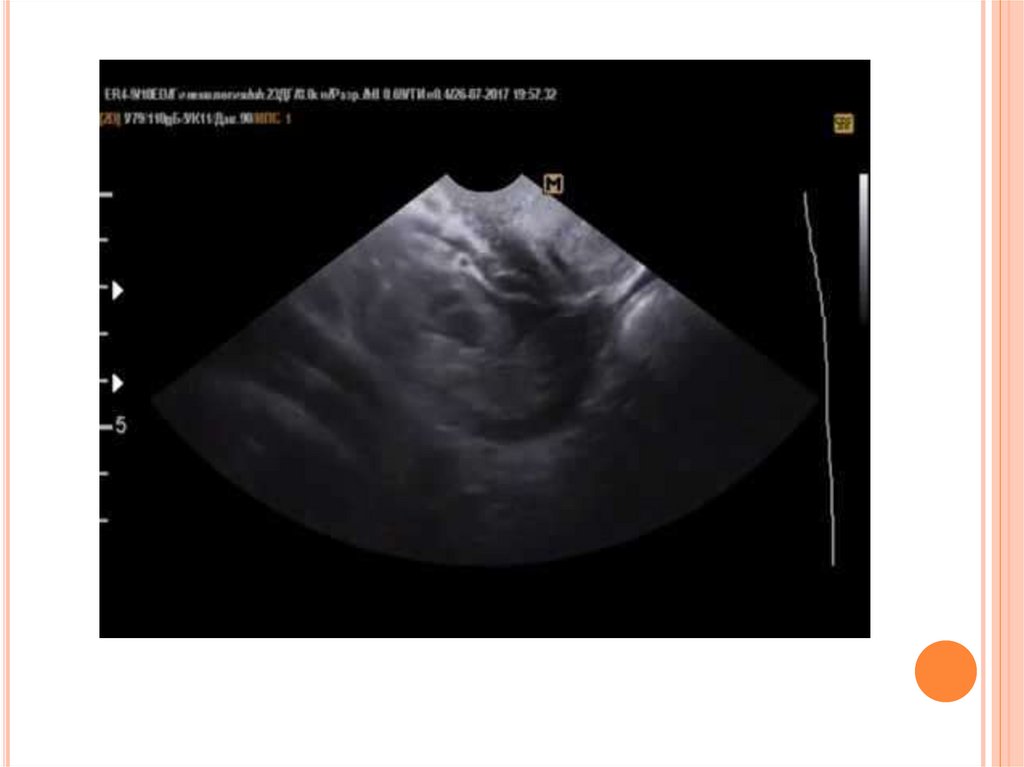

93. ДИАГНОСТИКА

диагностики является проведение ультразвукового исследования органов малого таза.

Наличие свободной жидкости позади матки – один из главных признаков повреждения

маточной стенки. Если диагноз неясен, а состояние пациентки ухудшается, проводят

лапароскопию.

при УЗИ – наличие образований- гематом и/или

свободной жидкости в брюшной полости.Снижение